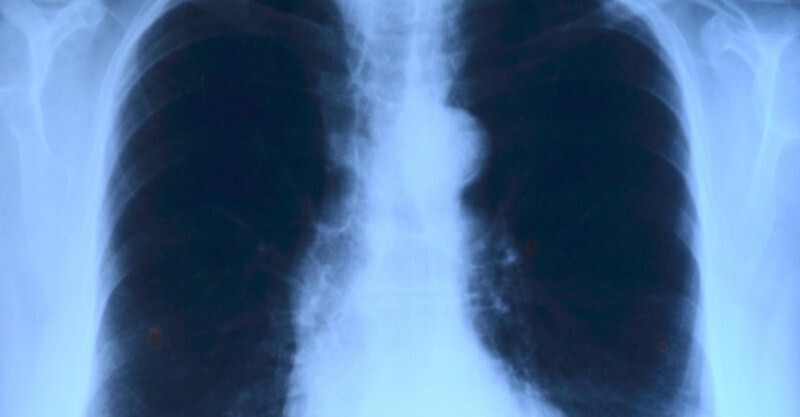

調查數據顯示,非吸煙者的肺癌發病率、增加了2倍,背後的主要致病因素便是廚房油煙!《柳葉刀》上曾刊登過一篇全球性的調研評估,將廚房煙霧污染列為重大健康問題隱患,排序僅次於高血壓、抽煙和酗酒。專家更是建議,勤勞刷鍋、清洗油煙機,以免一日三餐烹飪時,附著在廚房電器表面的油脂和食物殘渣,因再次加熱產生大量油煙,危害身體健康。